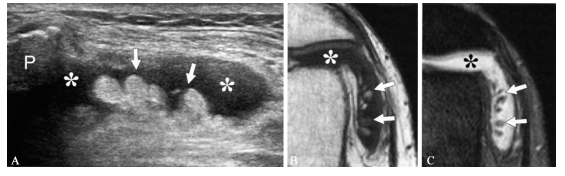

蔓状脂肪瘤,又称弥漫型滑膜脂肪瘤或滑膜绒毛样增殖,是一种罕见的单关节反应性病变,引 起 局 部 脂 肪-部 分 脂 肪 绒 毛 样 增生。它可能是原发的,或较常见的和其他关节病变相伴随,如退行性关节病、类风湿关节炎或以前的外伤。虽然偶尔有发生在髋关节、肩 关 节 或 肘 关 节 的 报 道,但是蔓状脂肪瘤最常发生在膝关节,特别是髌上隐窝。从临床的角度看,它可表现为长期的无痛性滑膜增厚和间断性的关节积液。蔓状脂肪瘤的超声表现为树样轮廓的团块和绒毛状突起,是因滑膜下 组 织 由 成 熟 的 脂 肪 组 织 代 替 所 致。一般情况下,肿瘤和滑 膜 组 织 相 比 回 声 多 伴 关 节 积 液 (图一A)。关节被动活动时,动态扫描可显示绒毛样突起来回弯曲和漂动。

如 怀 疑 蔓 状 脂肪瘤,应做 MRI检查确定诊断,所有脉冲序列的 MRI显示为叶状结构和类似脂肪的信号强度(图一B,C;)。

A. 膝关节髌骨旁隐窝侧面12~5MHz超声横断面显示关节内叶状、回声相对较高的团块(箭头),滑膜积液(* )使轮廓更清晰;P. 髌骨;T1 增强(B)和脂肪抑制 T2 增强(C)MRI横断面证实团块叶状突起的脂肪成分